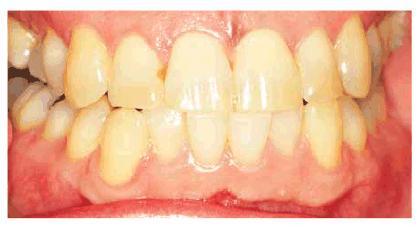

times may vary from 2 months to 1 year (Figures 16-28A 16-28B 16-28C 16-29A 16-29B 16-30A 16-30B 16-31A, and 16-31B). Patients are seen monthly to

replenish solutions and evaluate for continuing color change. Patients should

agree to a minimum of 2 months of nightly treatment before deciding to proceed

to more aggressive treatment. Fees are generally the cost of a monthly office

recall visit and additional material. Once lightening is observed, patients

should continue treatment until a month has passed with no obvious color

change. Dark tetracycline stains located in the gingival third of the tooth or

dark blue or gray stains have the least favorable prognosis. However, even in

these situations, there can be some improvement. This improvement may be

sufficient for the patient's esthetic demands. However, compliance by the

Figure 16-29A: Moderately tetracycline-stained teeth.

Figure 16-29B: In a research study, these teeth were bleached for 6 months nightly with a 10% carbamide peroxide. Not all results will be this good, especially if the discoloration is blue/gray or at the gingival third.